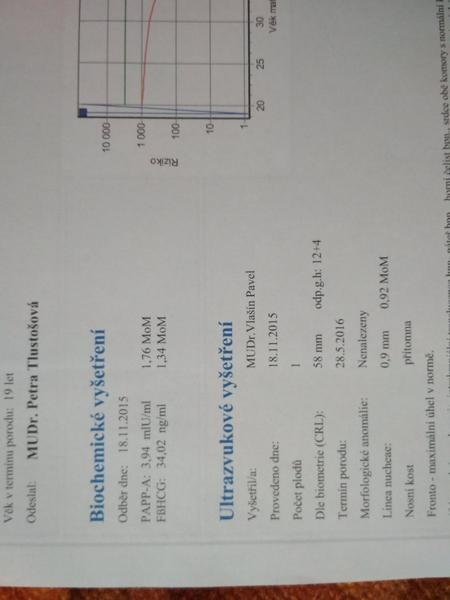

@seveneye mne ty hodnoty nic neříkají, posílám scan😉

@jednaholkaa já tam právě žádnou tu hodnotu volného Hcg nemám, jen to MoM

Ono se to zpřeházelo. Jsou tam vidět datumy.. 🙄

@jednaholkaa Tady jsem schválně našla ty výsledky z předchozích těhotenství 🙂 Obě to jsou holky 🙂 A hodnoty nízké 🙂 Teď zatím hodnoty nevím, na screening jdu ve čtvrtek :D